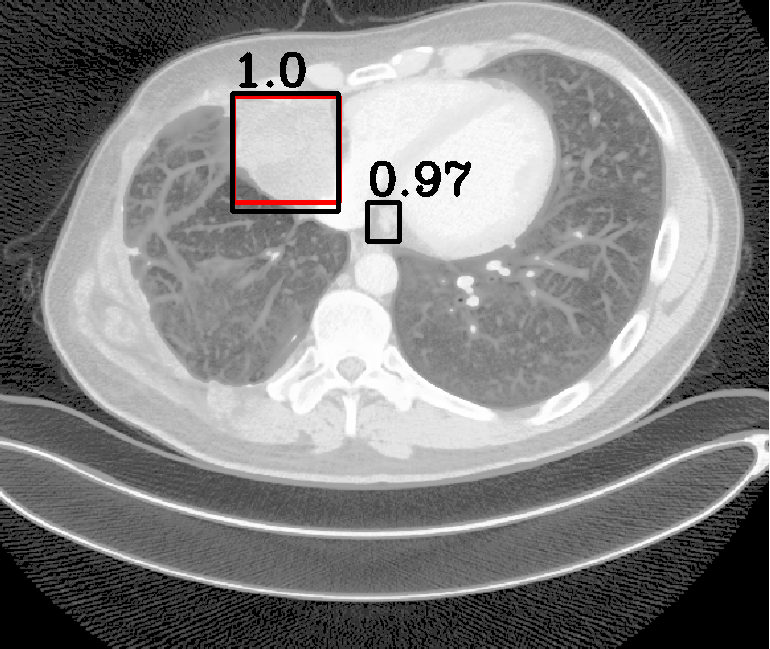

| (a) Ground Truth | (b) Faster R-CNN | (c) FPN | (d) Proposed |

In real-world scenarios, body lesions usually have arbitrary size. For instance, in the DeepLesion [14] dataset, the lesion size ranges from 0.21 mm to 342.5 mm. Since most of the established CNNs are not robust to handle such spatial scale variations, they have unpredictable behavior in the varying cases. As shown in Fig. 1, both Faster R-CNN and FPN fail to detect tiny lesions in the first row, while they produce small false positive lesions around the actual large lesion locations in the second and third rows.